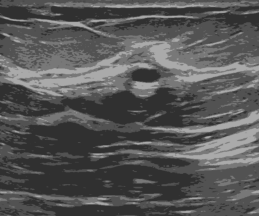

K Means++ is an unsupervised image segmentation algorithm that is an improved version of the popular K Means clustering algorithm (Arthur and Vassilvitskii, 2007). In medical image processing and analysis, K Means clustering has been utilized to segment interest areas from the background for spotting out the location and shape of cancerous cells (Ng et al., 2006). In K Means++, the interest area representing a better view to locate and analyze cancerous cells is segmented by inducing clusters or partitions where similar pixels of images are grouped into a certain category through an iterative process. Here, indicates the number of clusters to consider. This algorithm is relatively fast, computationally less expensive, and can easily be adapted to new unseen data. The effect of incorporating the K Means++ algorithm for Breast Ultrasound Image Segmentation is illustrated in the Figure 3. Here, Figure 3(a) represents original ultrasound image of Breast for patient having Benign Tumor and Figure 3(b) shows segmented image of that particular ultrasound image after incorporating K Means++ algorithm.

In this study, we have utilized the OpenCV implementation in Python for K Means++ with a -value of 4 and stopping criteria of if the maximum iterations are reached or specified epsilon/accuracy is reached. From the Figure, we can notice that the original ultrasound image has been segmented into clusters where the image pixels are stretched to their nearest most significant pixel values with normalization of 0 to 1.